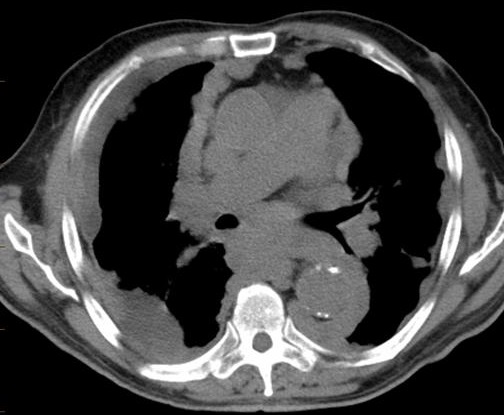

Aspect radiologique du

epaissisement pleurale d'une pleurite tuberculose au

stade restrictive de la plevre . La plevre est epais

, heterogene , hyperdense situe à la region

posterieure , inferieure du poumon droit |